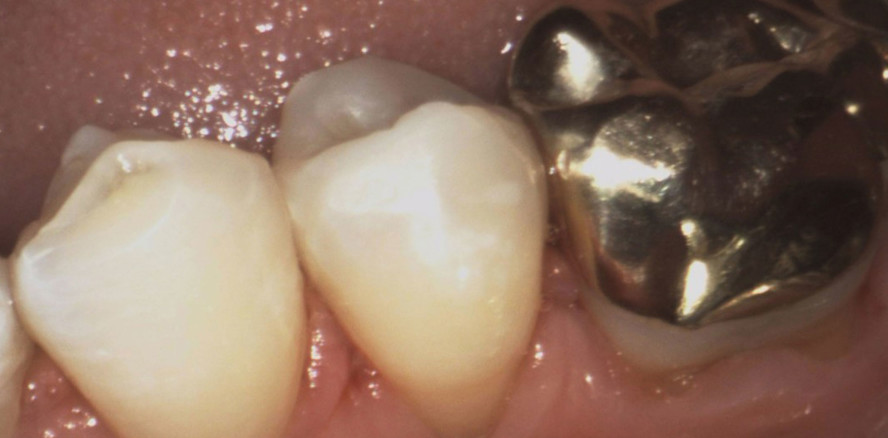

Austausch eines Goldinlays

Foto: Dr. Romy Kreplin

Bei der klinischen Kontrolluntersuchung einer 47-jährigen Patientin war am Zahn 35 ein dezenter Randspalt der alten Goldgussversorgung auffällig (Abb. 1 und 2). Die Patientin wünschte den Austausch der Restauration, weil für sie aufgrund der dunklen Zahnverfärbung auf der Bukkalseite des Zahnes das Risiko einer unbemerkten Karies in der Tiefe bestand (Abb. 2).